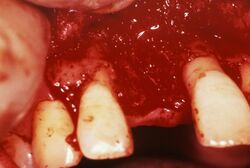

骨粗しょう症の人が歯周病になると、歯槽骨がもろくなり、悪化しやすいといわれている。